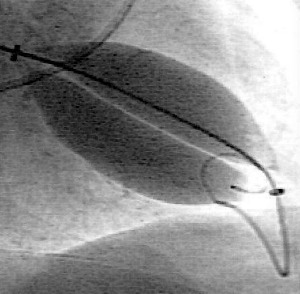

Double Balloon Mitral Valvuloplasty - Incredible Picture Guide • MyHeart

Double Balloon Mitral Valvuloplasty - Incredible Picture Guide • MyHeart myheart.net

mitral valve valvuloplasty balloon gradient double myheart incredible guide

Double balloon mitral valvuloplasty. Mitral valve disease. Mitral valve disease